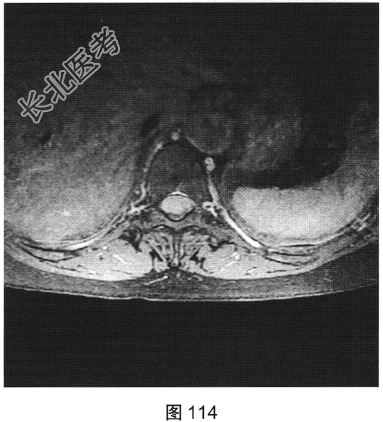

- [材料题] 患者女性,59岁,无明显诱因出现腰背部疼痛伴双下肢麻木1年,久行、久坐、久站或咳嗽、排便时疼痛加重,休息后症状缓解,1个月前腰背部麻木疼痛突发加重,行走100米既感疼痛难忍,伴双下肢无力疼痛。查体:脊柱无明显侧弯,相当于T10平面以下感觉减退,腰椎活动度受限,无紧张,棘突旁压痛、叩痛,向双下肢放射。挺腹试验阳性,跟臀试验(+),双侧直腿抬高试验(一),双下肢小腿外侧、足背感觉稍差,双侧

背伸肌肌力4级;肌张力正常,双侧巴宾斯基征可疑阳性。实验室检查:人类白细胞抗原B27阴性(一),RF<10U/ml(正常值0~15U/ml)。

- 多项选择题2.[提示]患者行MRI检查,如图111~图114所示。根据患者病史及影像学检查, 其最可能的诊断是( )